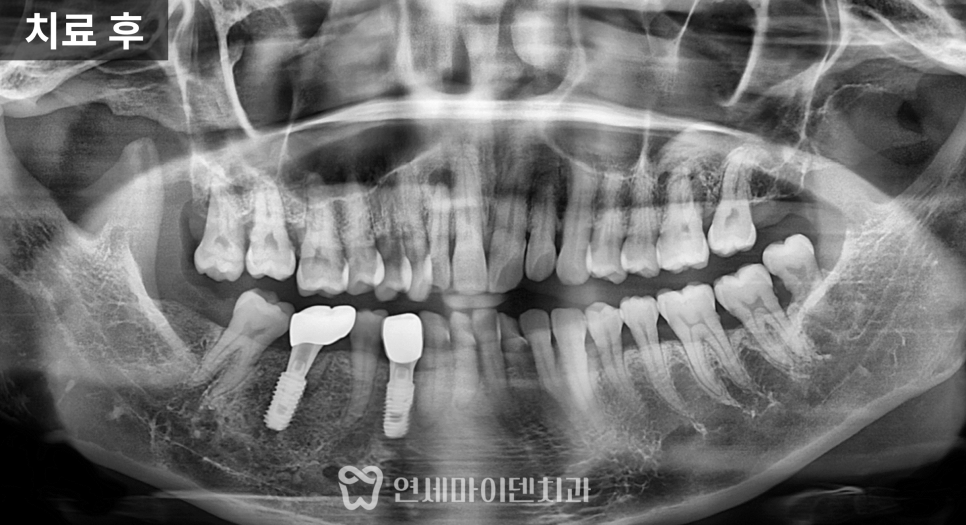

치료 전 방사선 사진을 보면

치아가 쓰러진 문제도 있었지만

무엇보다 뼈의 폭과 높이가

많이 줄어든 상태

였습니다.

잇몸도 전반적으로 약했고,

1차 수술: 발치, 염증 정리, 식립과 이식 동시 진행

첫 단계에서는

아래 1개, 위 2개

3개의 임플란트를 계획했습니다.

위쪽은 상악동이 내려와 있어

상악동 거상술과 뼈이식을 함께 시행한 뒤

그 공간에 임플란트를 식립했습니다.

아래쪽은 뼈 상태가 비교적 유지되어 있었지만

안정적인 고정을 위해

필요한 부위에 뼈이식을 병행했습니다.

3개월의 치유 기간을 거친 뒤

상부 구조를 연결하고

맞춤형 지대주를 형성한 후

보철을 완성했습니다.

이 시점부터 해당 부위로 식사가 가능해졌고

환자분의 생활 불편이 크게 줄었습니다.